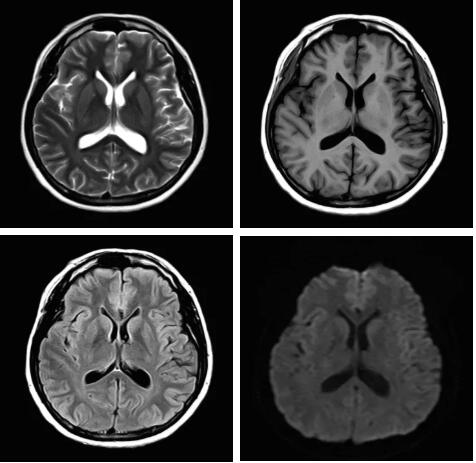

眾所周知,磁共振成像最核心的三個部分:磁體、梯度、射頻,此三部分為磁共振成像之魂,直接決定著磁共振成像的圖像質(zhì)量--圖像信噪比。各個廠家在磁共振成像提升圖像信噪比的道路上不斷探索和創(chuàng)新,致力于信噪比的提升,各個廠家側(cè)重點不同,在各自領(lǐng)域各有所長,在本世紀第二個十年,各個廠家都在做不同的嘗試和改進,例如:A廠家的“太空艙”技術(shù),旨在解決射頻發(fā)射和射頻接收的實時互補……;B廠家的ADC前置所謂的“全數(shù)字”技術(shù),旨在解決信號模數(shù)轉(zhuǎn)換的時間早晚……;C廠家的“光纖”技術(shù),旨在解決信號傳輸路徑的信號損失……;各家都在一定程度上解決了信號的損失,信噪比在一定程度上有所提升,但是并未從根本上解決信噪比大幅度提升。

佳能公司在2018年率先提出了Pure射頻成技術(shù),從源頭上解決信噪比的提升,著眼于全路徑、全成像鏈的優(yōu)化和改進。

3.Pure射頻成像鏈

從成像源頭的磁體采用鍍膜新磁體高密度薄層鍍膜貼合技術(shù),獲得更好的磁場均勻度,奠定磁共振成像基礎(chǔ);采用3D RSCE微雕梯度精準控制頻率和相位,輸出理想波形,實現(xiàn)渦流的“0”殘余,還原最真實的圖像信息;射頻接收端通過計算機人工智能對信號抗干擾處理,把信號放大并去除梯度、磁場等對信號干擾,再經(jīng)過二次人工智能信號識別,去除噪聲污染獲得純凈的信號;通過Pure射頻成像鏈的優(yōu)化和改進使信噪比提升40%,這是磁共振領(lǐng)域革命性的顛覆和改變。